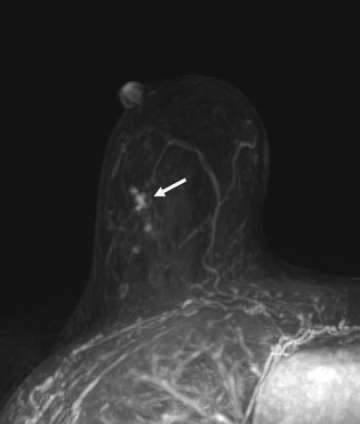

Calcifications are best visualized on mammography, and thus this modality plays a crucial role in screening for DCIS; however other imaging modalities may also provide additional information that can suggest a diagnosis of DCIS. Ultrasound may be utilized when calcifications are identified on mammogram to look for solid components, which may aid in ultrasound-guided biopsy. On ultrasound, calcified DCIS may appear as echogenic foci within a mass or duct. Noncalcified DCIS may have a similar appearance, but without posterior acoustic shadowing. In addition, internal vascularity can also help to improve the positive predictive value.7 On MRI, enhancement patterns play a large role, with linear or segmental non-mass enhancement most commonly associated with DCIS, regardless of MRI kinetics (Figure 2).8